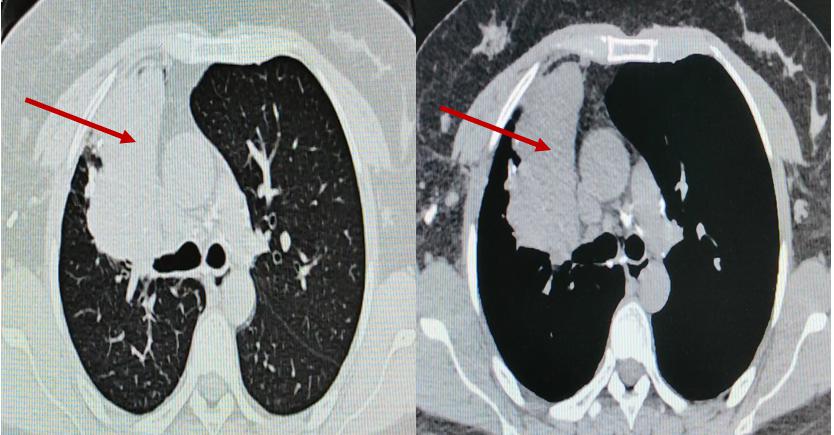

▲术前胸部CT

患者为36岁女性,既往有肺结核病史,近两年反复出现低热、咳嗽症状,胸部CT提示右肺上叶大片实变、坏死及多发黏液栓,气管镜显示支气管瘢痕性闭塞,化验提示曲霉菌感染。患者曾接受长期口服抗真菌药物治疗,但病灶未缩小,并出现视神经损害等药物并发症,停药后病情仍反复,右肺出现新发病灶。

入院后,呼吸与危重症医学科介入团队对患者病情进行全面评估。完善胸部增强CT提示:右肺上叶大片状实变并坏死,支气管完全闭塞。由于前期单纯口服抗真菌药物效果不佳,因此联合气管镜下介入治疗势在必行。经过认真评判,团队制定了详细的气管镜下介入诊疗计划。治疗过程包括:超声支气管镜引导下精准穿刺,高频电刀微创开窗建立引流通道;钳夹清除远端大量坏死组织;局部灌注抗真菌药物以提高病灶药物浓度;结合球囊扩张与超细冷冻冻融治疗,扩大引流窗口;并多次行镜下冲洗,彻底清除分泌物与坏死物。